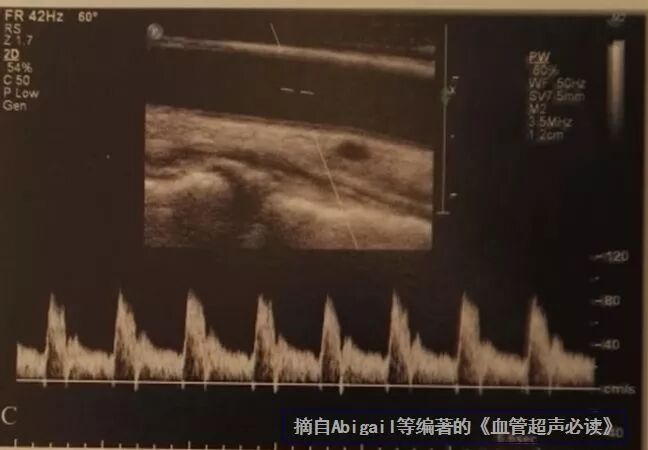

下图中,血管斜角较大,θ角为46°

什么是超声容积探头血流量测定 |取样容积和角度θ_https://www.jmylbn.com_新闻资讯_第7张

大多数肱动脉从肘部到桡尺分叉这一段有一个自然的斜角,可以利用这个天然角度。